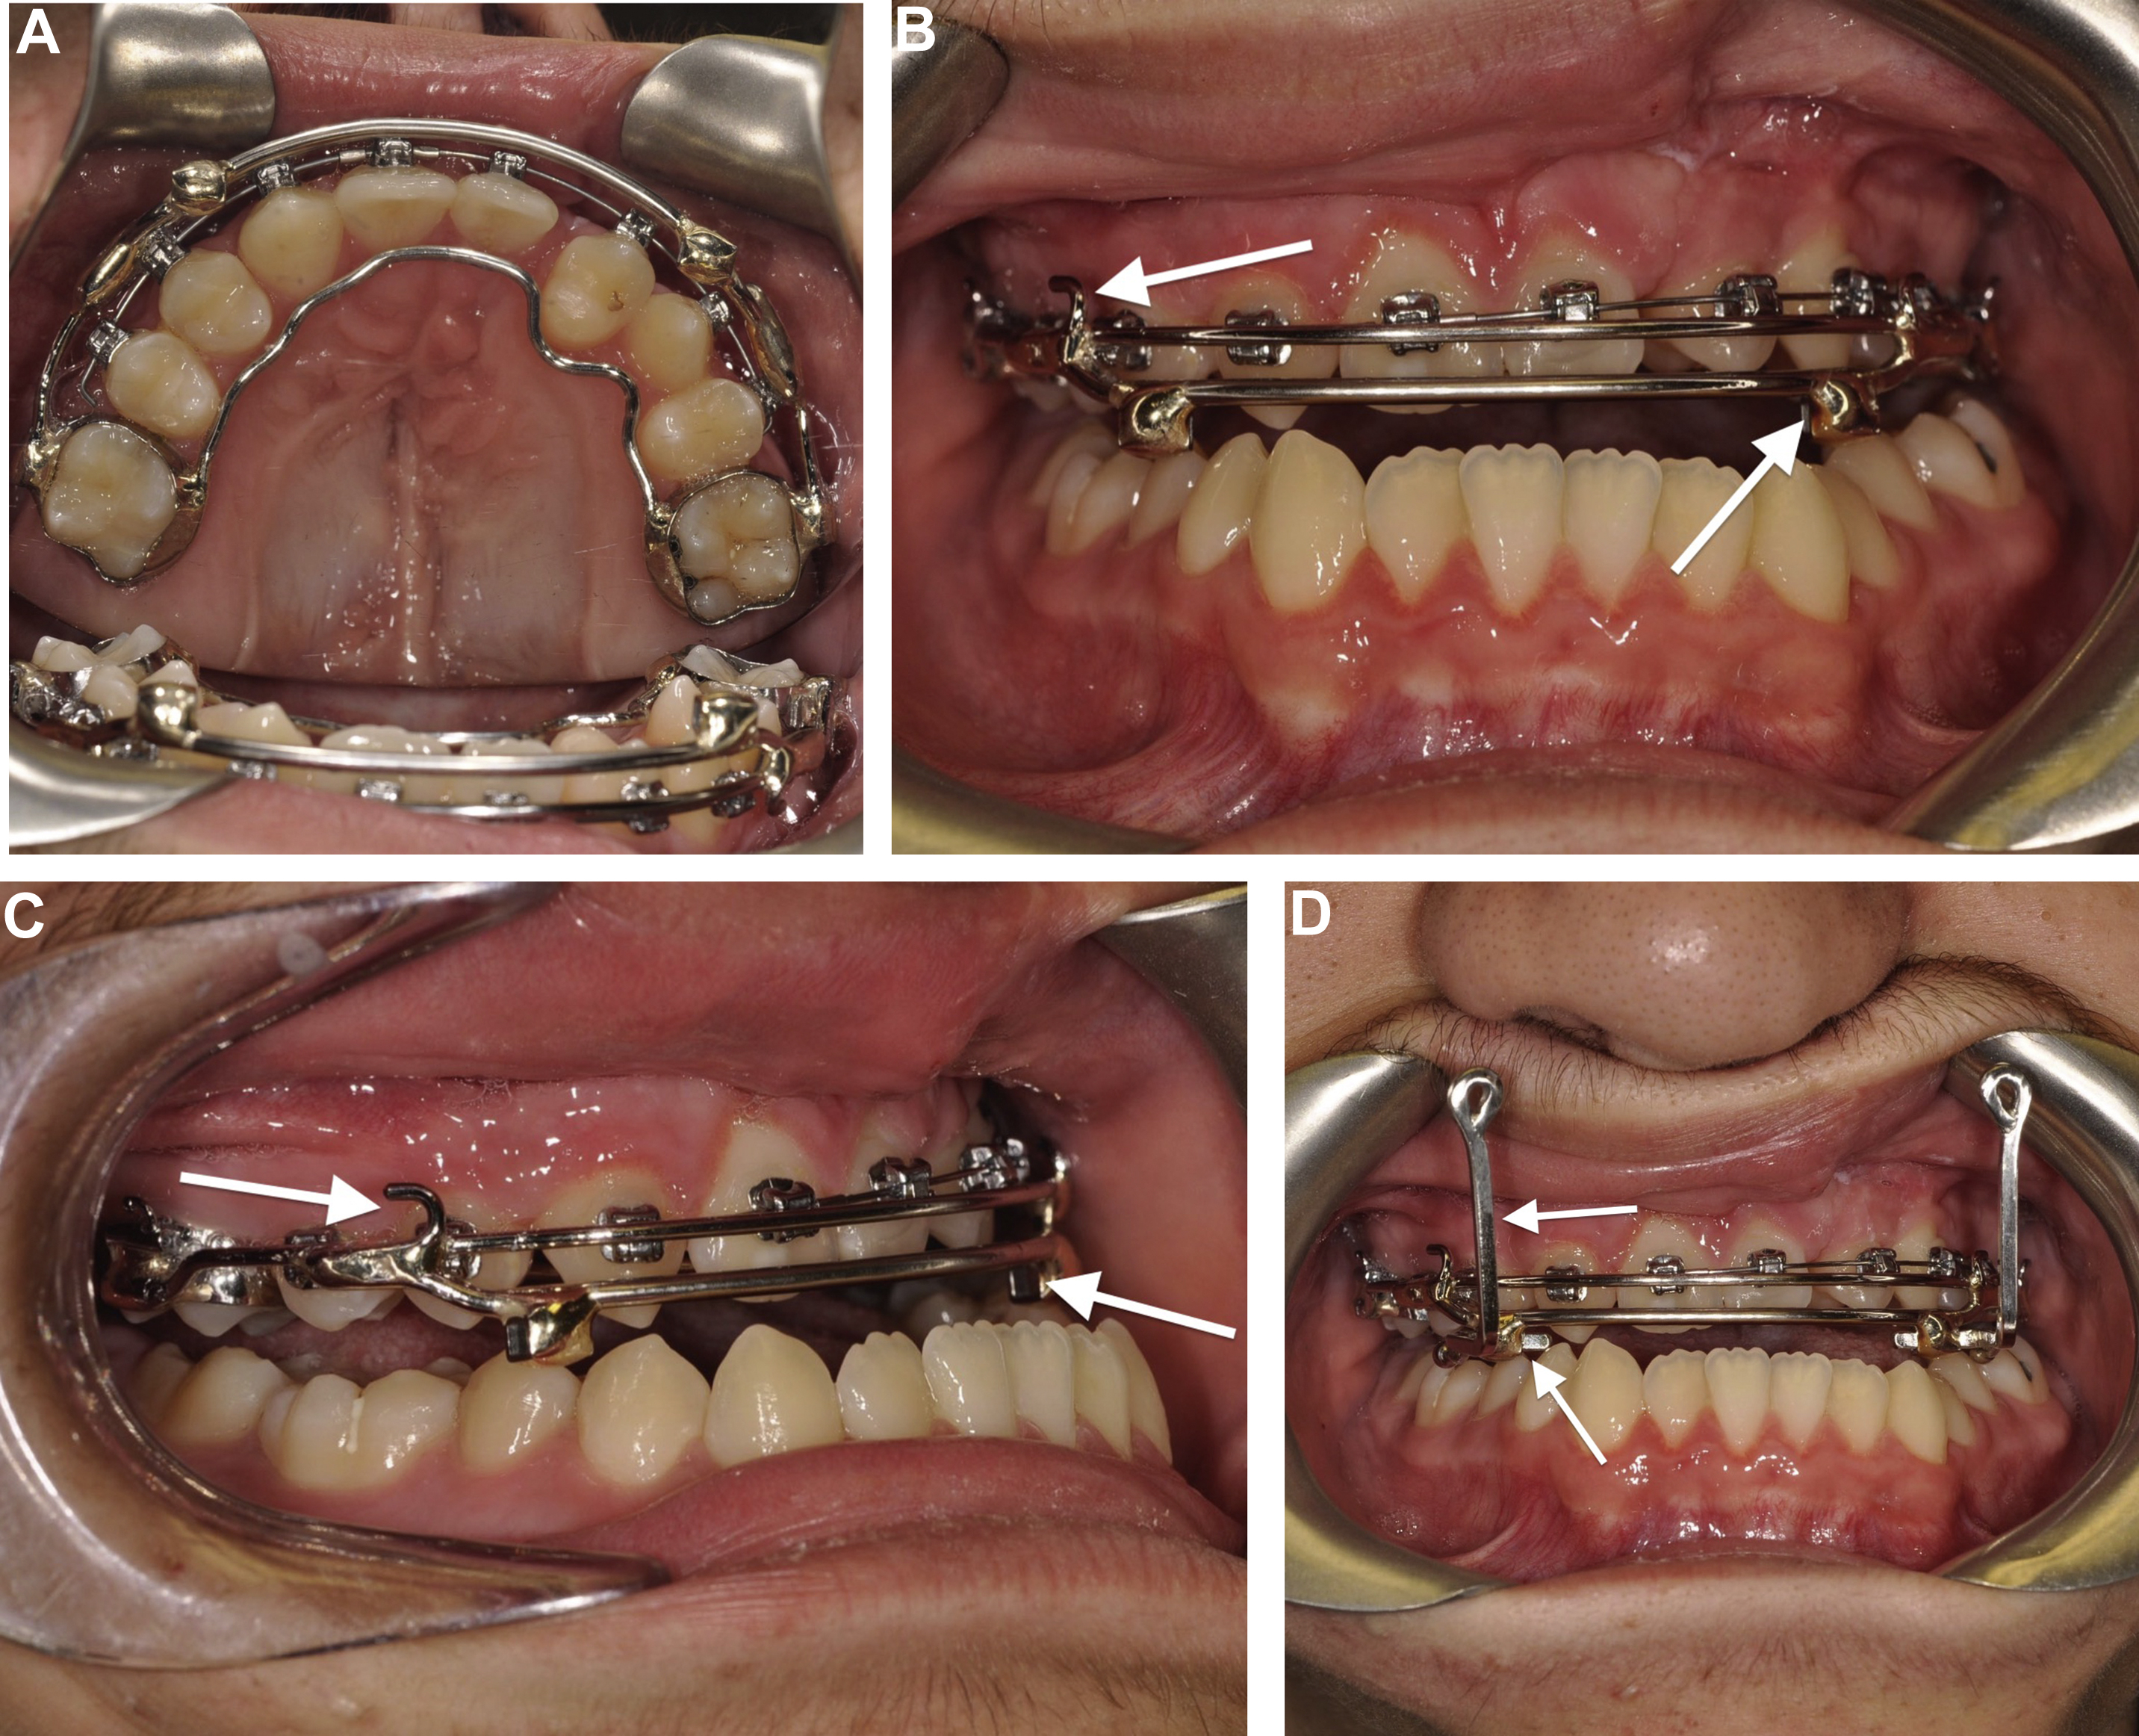

Intraoral Splint

For both external and internal distraction devices, the authors use 0.040″ stainless steel wire conformed to the labial and palatal aspects of the dental arch and soldered to the first molar bands ( Fig. 3 A–C). If desired, additional teeth can be incorporated for added retention of the appliance. In younger patients undergoing RED distraction, maxillary second primary molars can be used to support the splint if they have adequate root support and are stable. The RED splint has 2 square tubes just medial to the oral commissures that are used to secure 2 removable rectangular hooks, which connect the intraoral splint to distraction screws mounted onto the RED system. , The height of the traction hooks is such that they are level to or above the palatal plane for vector control (see Fig. 2 ; Fig. 3 D).